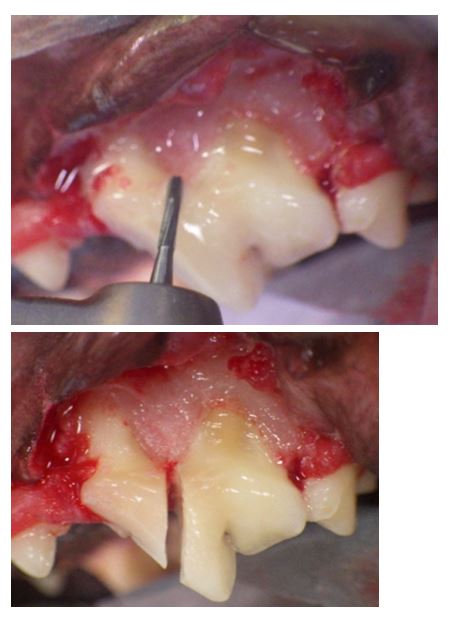

Un large lambeau d’accés permet d’aborder les tissus sous gingivaux et en particulier l’os alvéolaire recouvert de son périoste.La dissection sous périostée découvre l’os alvéolaire.

Sa découpe en plastron facilite l’extraction car la dent est cueillie dans son alvéole sans difficulté. Cette technique, l’alvéolotomie, est la technique de choix pour les avulsions de dents courbes et volumineuses (canines maxillaires de grands chiens).

*L’extraction des dents à racines multiples pose plus de problèmes en raison de la nature convergente ou divergente des racines. Il est indispensable de sectionner ces dents en autant de morceaux que de racines avant de les extraire séparément comme des dents monoradiculées . Cette séparation inter-radiculaire s’effectue soit avec une turbine équipée d’une fraise fissure soit avec un contre-angle equipé d’un disque diamanté.